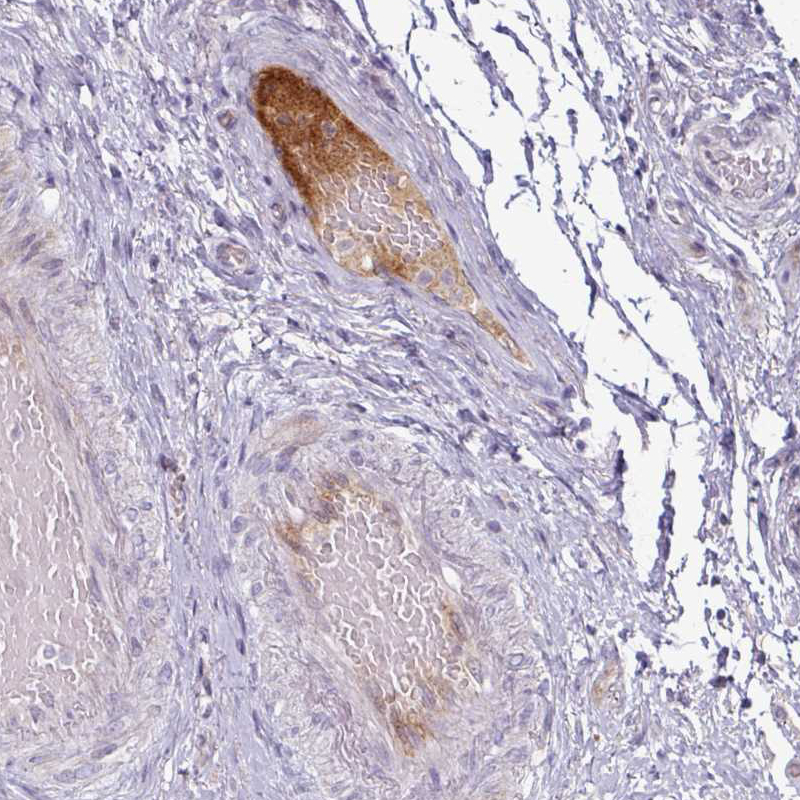

Immunohistochemical staining of human urinary bladder shows moderate positivity in plasma in blood vessels.